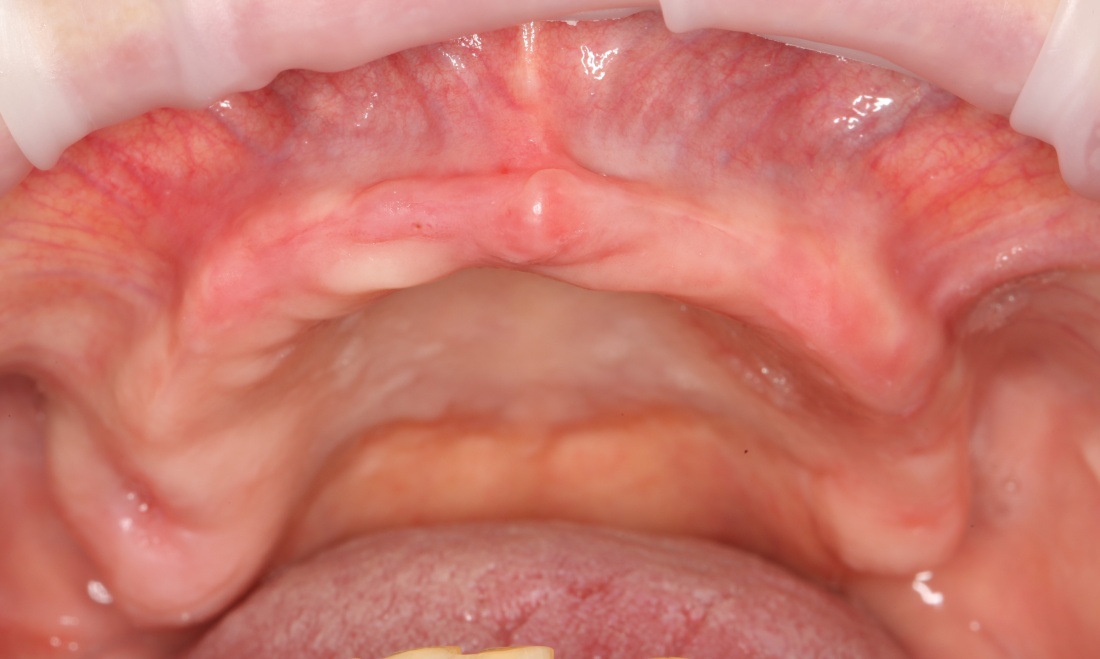

Простой пример. Возьмём один и тот же клинический случай — полную потерю зубов вследствие удаления на одной из челюстей. Что-то типа этого:

И вот представьте, что с подобной клинической картиной обращаются два человека.

Второй пациент — 80-летняя бабушка, большую часть своей жизни пользующаяся полным съёмным протезом. Какие имплантологические решения мы им предложим и от чего они будут зависеть? Ведь вариантов достаточно много.